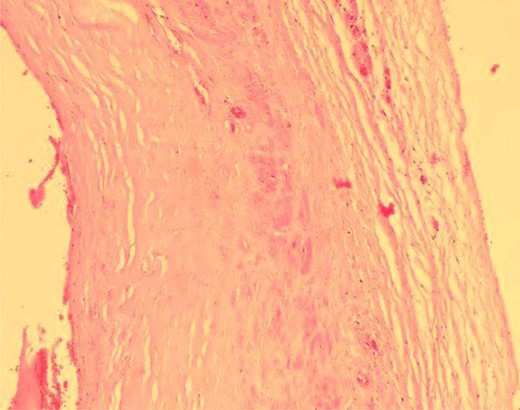

Under local anaesthesia, the aneurysm site was incised. A saccular aneurysm of 2-by-1.5 cm appeared at the distal part of the radial artery. Using vessel loops, the artery was controlled proximal and distal to the aneurysm (Fig. 4). After clamping the artery, a Doppler examination was conducted and indicated positive signals over the thumb and digital arteries. Then, artery ligation followed by aneurysm excision was done. The post-operative period was uneventful. Later, the histopathology report showed a dilated arterial sac with a complete fibromuscular wall and an organized thrombus attached to its lumen (Fig. 5).

Microscopic view of the aneurysmal wall shows the muscular layer.